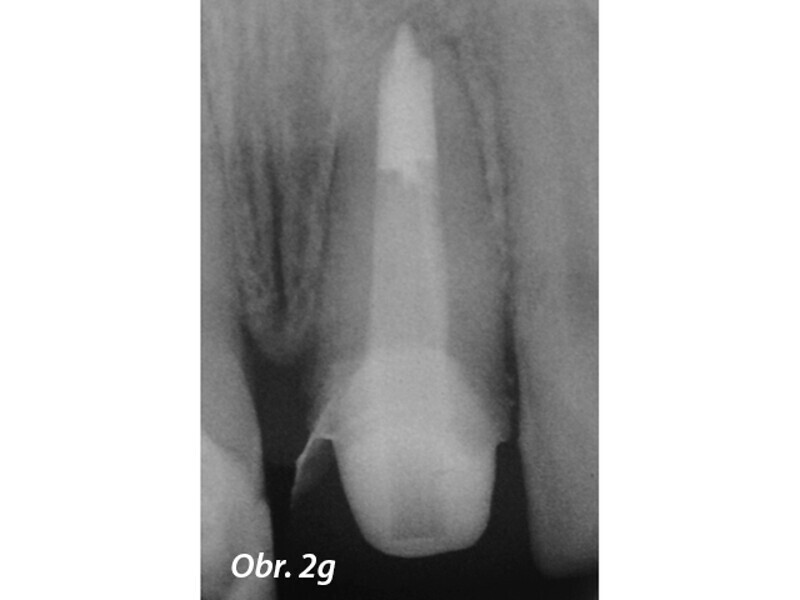

Aplikace MTA s použitím Produit Dentaires (PD) MAP System